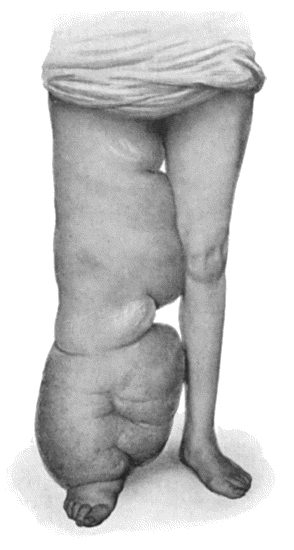

| 89. | Elephantiasis Neuromatosa in a woman æt. 28 | 359 |

| 97. | Elephantiasis in a woman æt. 45 | 387 |

| 98. | Elephantiasis of Penis and Scrotum | 388 |